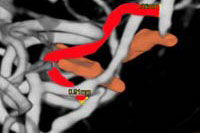

Las mayores dificultades que hay que enfrentar, asegura, son la ubicación de estos aneurismas, a veces entre los lóbulos cerebrales del paciente, como es el caso de este primer bypass intra-intra. Otra, que el diámetro de estas arterias es submilimétrico: en este caso, medía 0,91 milímetros -lo que medirían nueve cabellos juntos-, lo que explica que solamente en la sutura vascular se haya demorado 100 minutos, de una operación total de 18 horas.

El paciente afectado, informa el doctor, era un hombre joven de Talca que consultaba por una persistente cefalea. "Un scanner reveló una imagen redondeada entre el lóbulo temporal y parietal; luego, una angiografía tridimensional mostró que era un aneurisma no susceptible de tratamiento habitual. Dado que habían tres arterias comprometidas, en una se hizo un bypass extra-intra craneano, y en otro uno intra-intra". El enfermo evolucionó muy favorablemente, quedó sin secuelas y ya se encuentra en su casa.